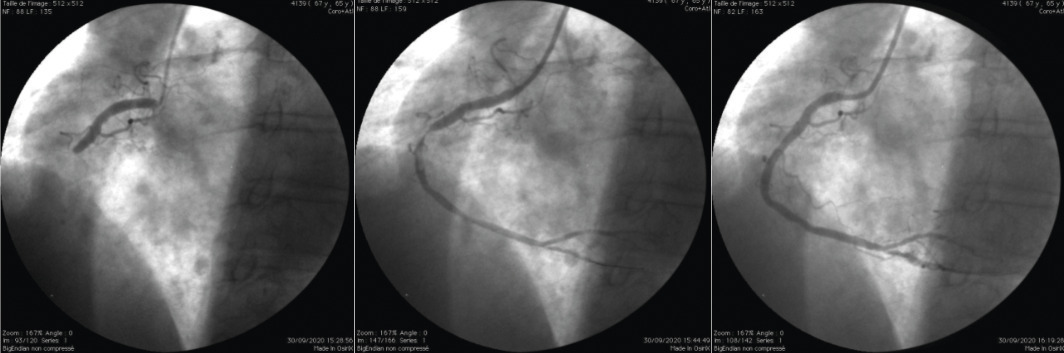

En dehors des dissections coronariennes spontanées, des spasmes ou des emboles coronariens, les syndromes coronaires aigus (SCA) résultent le plus souvent de la rupture dans la lumière artérielle d’une plaque athéromateuse. S’ensuit la formation d’un thrombus dont l’évolution imprévisible peut conduire à l’occlusion coronarienne et à la mort subite (fig. 2 ). Si une telle atteinte coronarienne menaçante est cliniquement suspectée, une coronarographie est réalisée dans un délai qui dépend des symptômes, de l’ECG et des dosages biologiques (troponinémie) [fig. 3 ].

fig. 4 ) si elle peut être réalisée moins de 120 minutes après le diagnostic.4

Si l’accès à une salle de cathétérisme cardiaque n’est pas immédiatement possible et qu’une fibrinolyse intraveineuse est entreprise, une coronarographie devra être réalisée entre deux et vingt-quatre heures après, afin de s’assurer de la perméabilité de l’artère et de réaliser si nécessaire une angioplastie complémentaire.5

Avec sus-décalage du segment ST

La coronarographie permet d’identifier l’artère responsable, dont l’angioplastie primaire reste le traitement idoine (Si l’accès à une salle de cathétérisme cardiaque n’est pas immédiatement possible et qu’une fibrinolyse intraveineuse est entreprise, une coronarographie devra être réalisée entre deux et vingt-quatre heures après, afin de s’assurer de la perméabilité de l’artère et de réaliser si nécessaire une angioplastie complémentaire.5